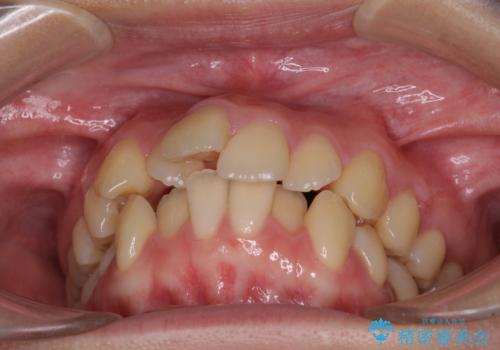

- 前歯のデコボコと突出感を気にして来院された患者様です。

上下左右第一小臼歯4本を抜歯して、積極的に口元を引っ込めるよう、ワイヤー装置にて矯正治療を行うこととしました。

口の閉じにくさが改善され、横顔のシルエットも大幅に改善されました。